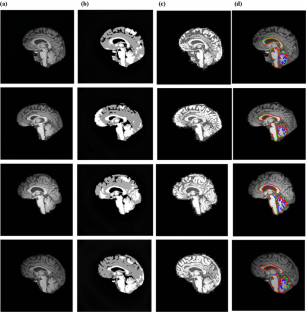

Segmentation and texture analysis of structural biomarkers using neighborhood-clustering-based level set in MRI of the schizophrenic brain

Schizophrenia (SZ) is a psychiatric disorder that especially affects individuals during their adolescence. There is a need to study the subanatomical regions of SZ brain on magnetic resonance images (MRI) based on morphometry. In this work, an attempt was made to analyze alterations in structure and texture patterns in images of the SZ brain using the level-set method and Laws texture features.

T1-weighted MRI of the brain from Center of Biomedical Research Excellence (COBRE) database were considered for analysis. Segmentation was carried out using the level-set method. Geometrical and Laws texture features were extracted from the segmented brain stem, corpus callosum, cerebellum, and ventricle regions to analyze pattern changes in SZ.

The level-set method segmented multiple brain regions, with higher similarity and correlation values compared with an optimized method. The geometric features obtained from regions of the corpus callosum and ventricle showed significant variation (p < 0.00001) between normal and SZ brain. Laws texture feature identified a heterogeneous appearance in the brain stem, corpus callosum and ventricular regions, and features from the brain stem were correlated with Positive and Negative Syndrome Scale (PANSS) score (p < 0.005).